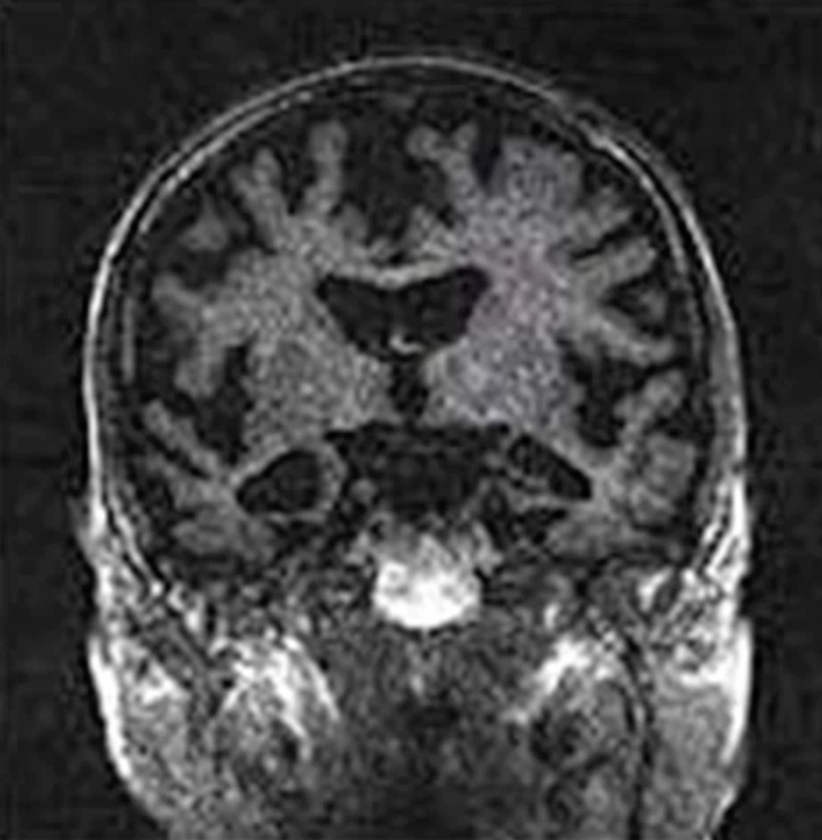

Diag?

Alzheimers